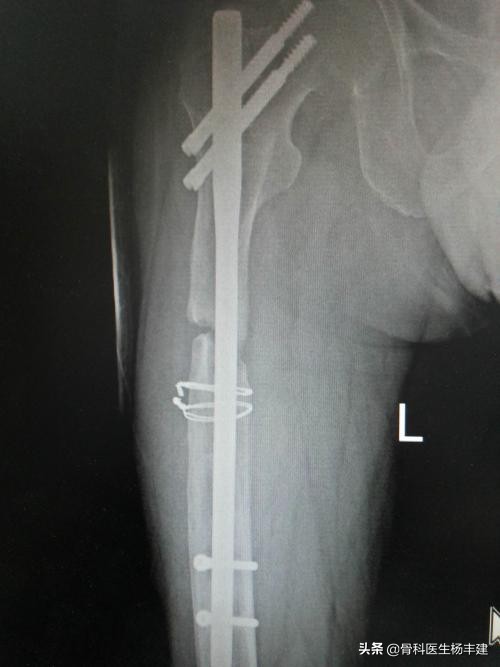

大腿骨固定后9个月,出现钢板断裂的病例